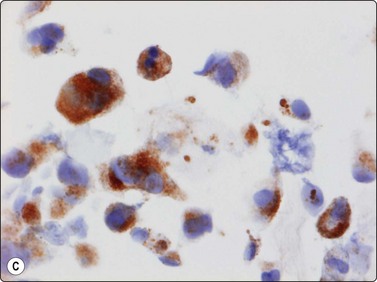

The Langerhans cell histiocytes express S-100 protein and CD1-antigen (Fig. 16.11). According to the Histiocyte Society the definitive diagnosis of Langerhans cell histiocytosis is based on the demonstration of Birbeck granules by electron microscopy or positivity for CD1 antigen.15 The examination of conventionally stained material gives a presumptive diagnosis. The cytological features of Langerhans cell histiocytosis has been recorded in several series.16-18

image image

Fig. 16.11 Langerhans cell histiocytosis (eosinophilic granuloma)

The Langerhans cell histiocytes express (A) S-100 protein and (B) CD1-antigen (Cell block, immunoperoxidase).